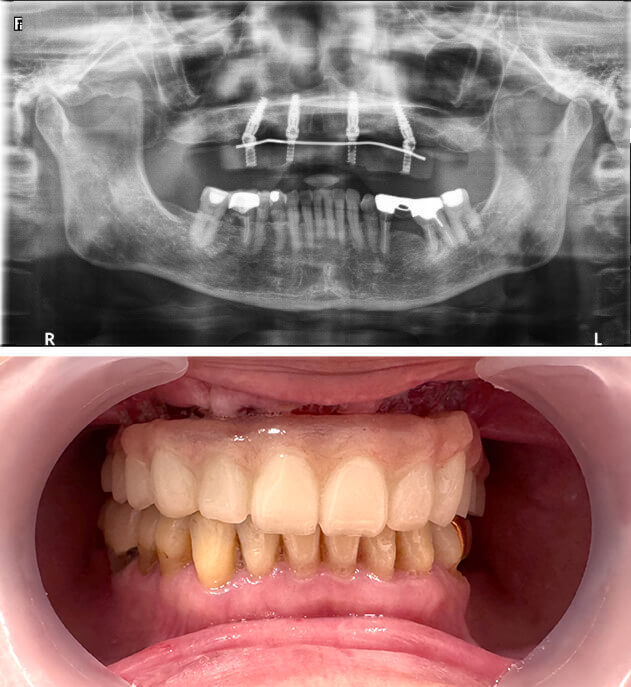

案例圖片

案例說明

● 口腔狀況:上顎無牙

● 治療時間:當天有牙

● 植體數量:4 根

● 假牙類型:上顎、整座固定假牙